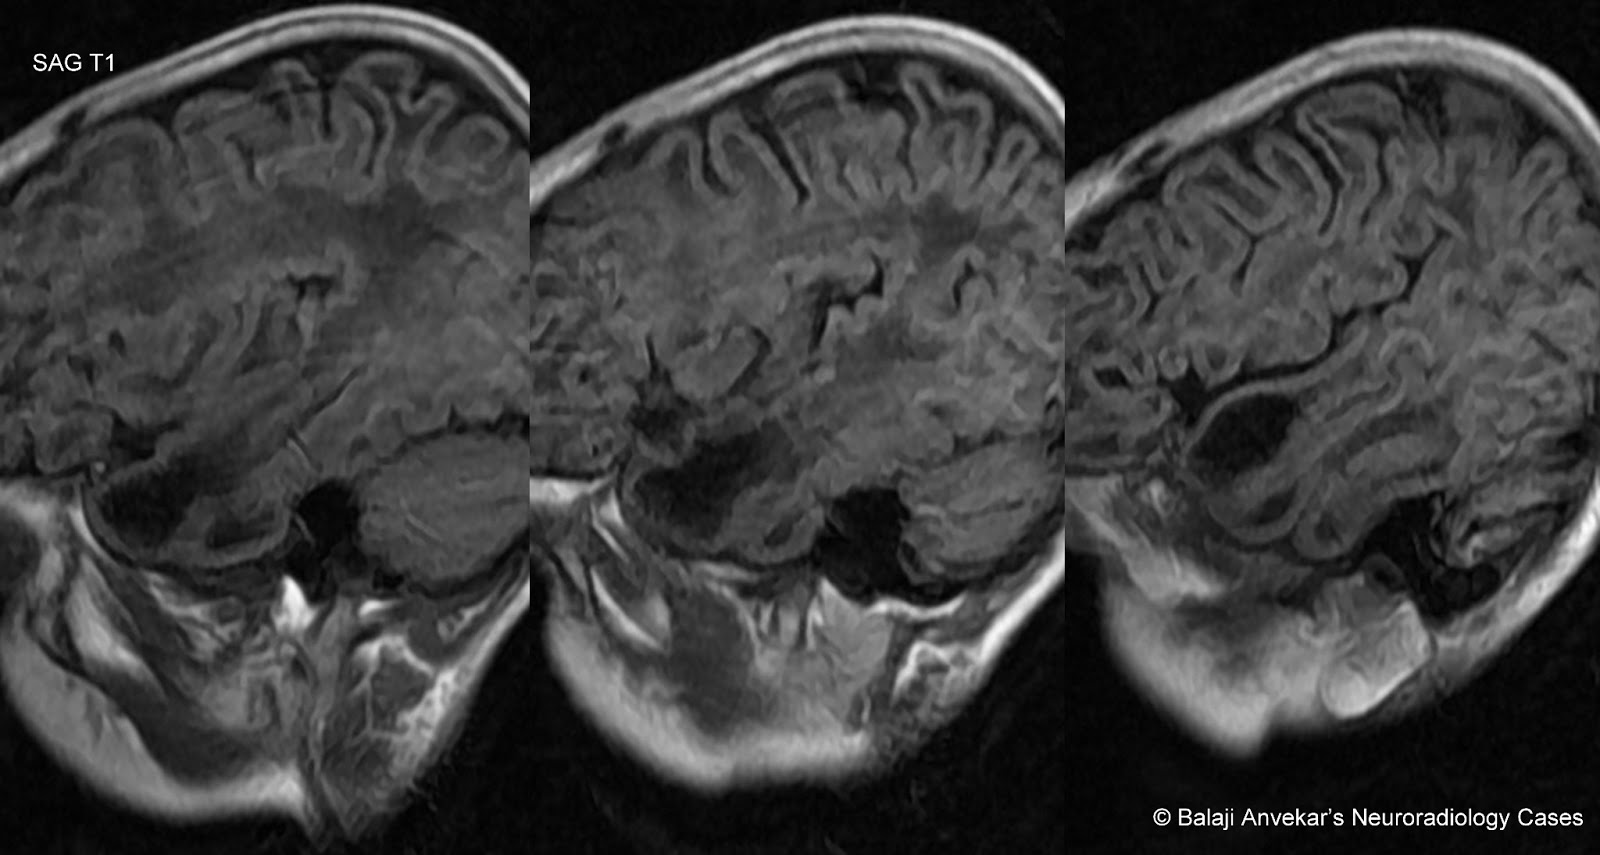

From www.neuroradiologycases.com

Dr Balaji Anvekar FRCR Van Der Knaap Leukoencephalopathy MRI Radiology Van Syndrome The growth of cysts or tumors. It is named after the two doctors who first described the disease, and affects. vhl is a rare disorder caused by a faulty gene. the authors provide an updated review of the molecular cytogenetics and clinical features of. Radiology Van Syndrome.